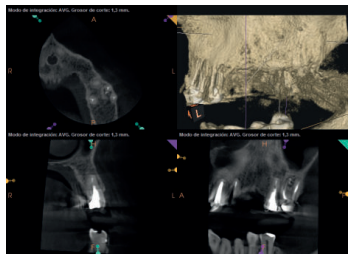

A los seis meses el paciente acudió a revisión sin ninguna sintomatología, tanto a nivel anterior como posterior. En las radiografías periapicales se apreció una disminución en el tamaño de las lesiones periapicales radiolúcidas preexistentes (Figuras 10 y 11). Dado que faltaba tratar la lesión del 25, se realizó CBCT de control donde se comprobó la mejoría a nivel del 26 (Figura 12), por lo que se programó la microcirugía del 25.

Una vez realizada la microcirugía del 25, el paciente no volvió a presentar ninguna sintomatología y las tomografías de control a 12 meses (en 25) y a 18 meses en los dientes restantes mostraron la regeneración de las lesiones periapicales radiolúcidas preexistentes en todos los dientes tratados (Figuras 13 a 16).

Se realizaron controles radiológicos a los 6, 12 y 18 meses mediante CBCT, apreciándose ausencia de sintomatología y reversión del cuadro infeccioso crónico, así como progresividad y estabilidad en la regeneración ósea apical. A nivel del 21 se aprecia radioopacidad periapical, sin pérdida de volumen, y ausencia de invasión del espacio preservado por el tejido blando circundante. Si bien algunos autores han utilizado plasma rico en factores de crecimiento (PRGF) asociado a Bio-Oss® y Bio-Gide® en casos similares al nuestro, hemos obtenido un resultado adecuado sin aplicar PRGF como técnica complementaria13.